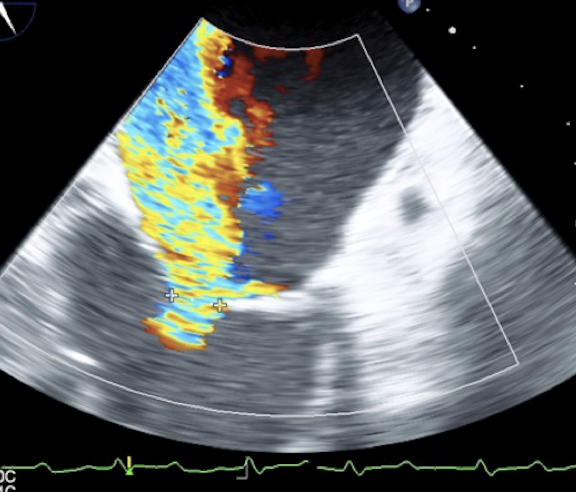

Cardiac 2 Valves Mitral Valve from TEE Image